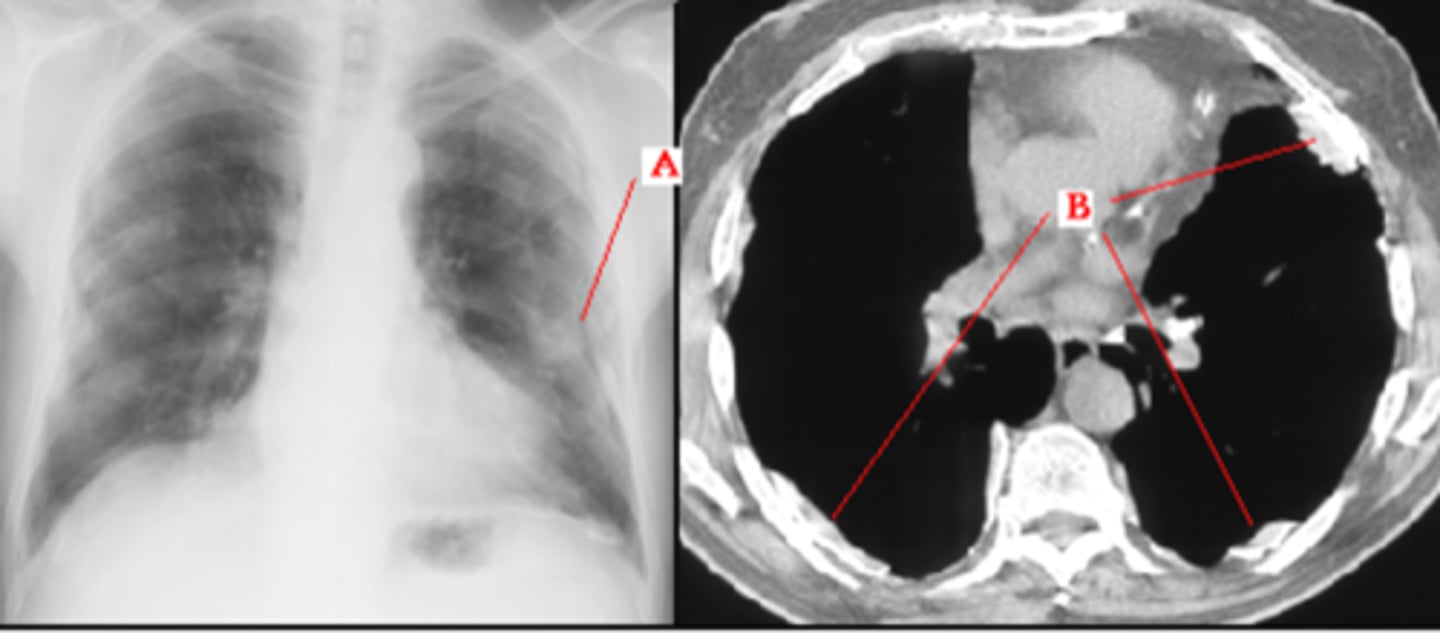

congestive heart failure

congestive heart failure

CHF - severe alveolar infiltrate